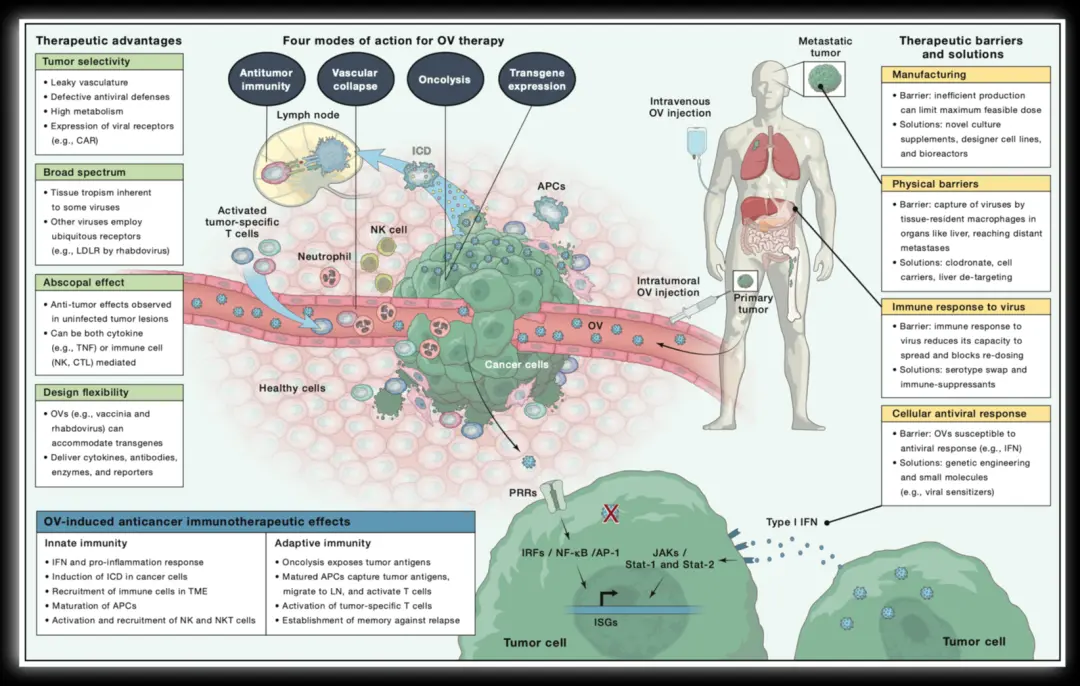

来,实现下面的图

本文详细指导如何使用图形设计软件,通过矩形和椭圆工具,配合钢笔工具,一步步绘制人体细胞和器官,包括细胞群组的虚化效果和肿瘤细胞的绘制过程,以及排版技巧。

本文详细指导如何使用图形设计软件,通过矩形和椭圆工具,配合钢笔工具,一步步绘制人体细胞和器官,包括细胞群组的虚化效果和肿瘤细胞的绘制过程,以及排版技巧。